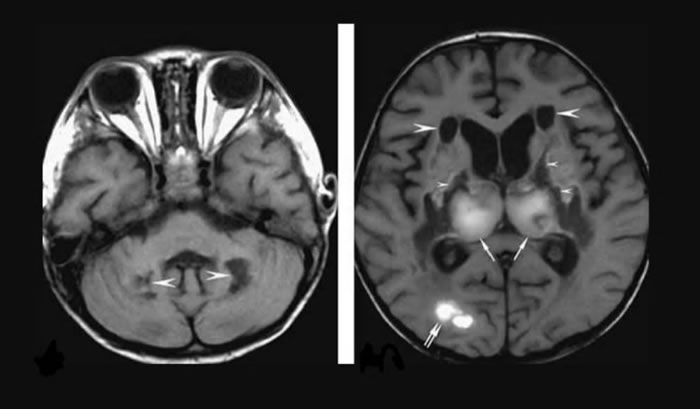

医生将此诊断为“急性坏死性脑病变”(acute necrotizing encephalopathy),是流感和其他病毒感染的罕见并发症。

当时,医生也进行了CoViD-19测试,结果呈阳性。但病人身上出现的是新冠病毒疫情下的非典型症状,于是决定对其进行CT检查。扫描显示,病人大脑中负责记忆和传递信号的部分受损。结果,医生确诊,病人患上了急性坏死性脑病(acute necrotizing encephalopathy,ANE)。这是一种罕见的、严重的、经常会致命的疾病,在发生病毒性感染时就会发生。医生们都认为,罪魁祸首就是CoViD-19病毒。